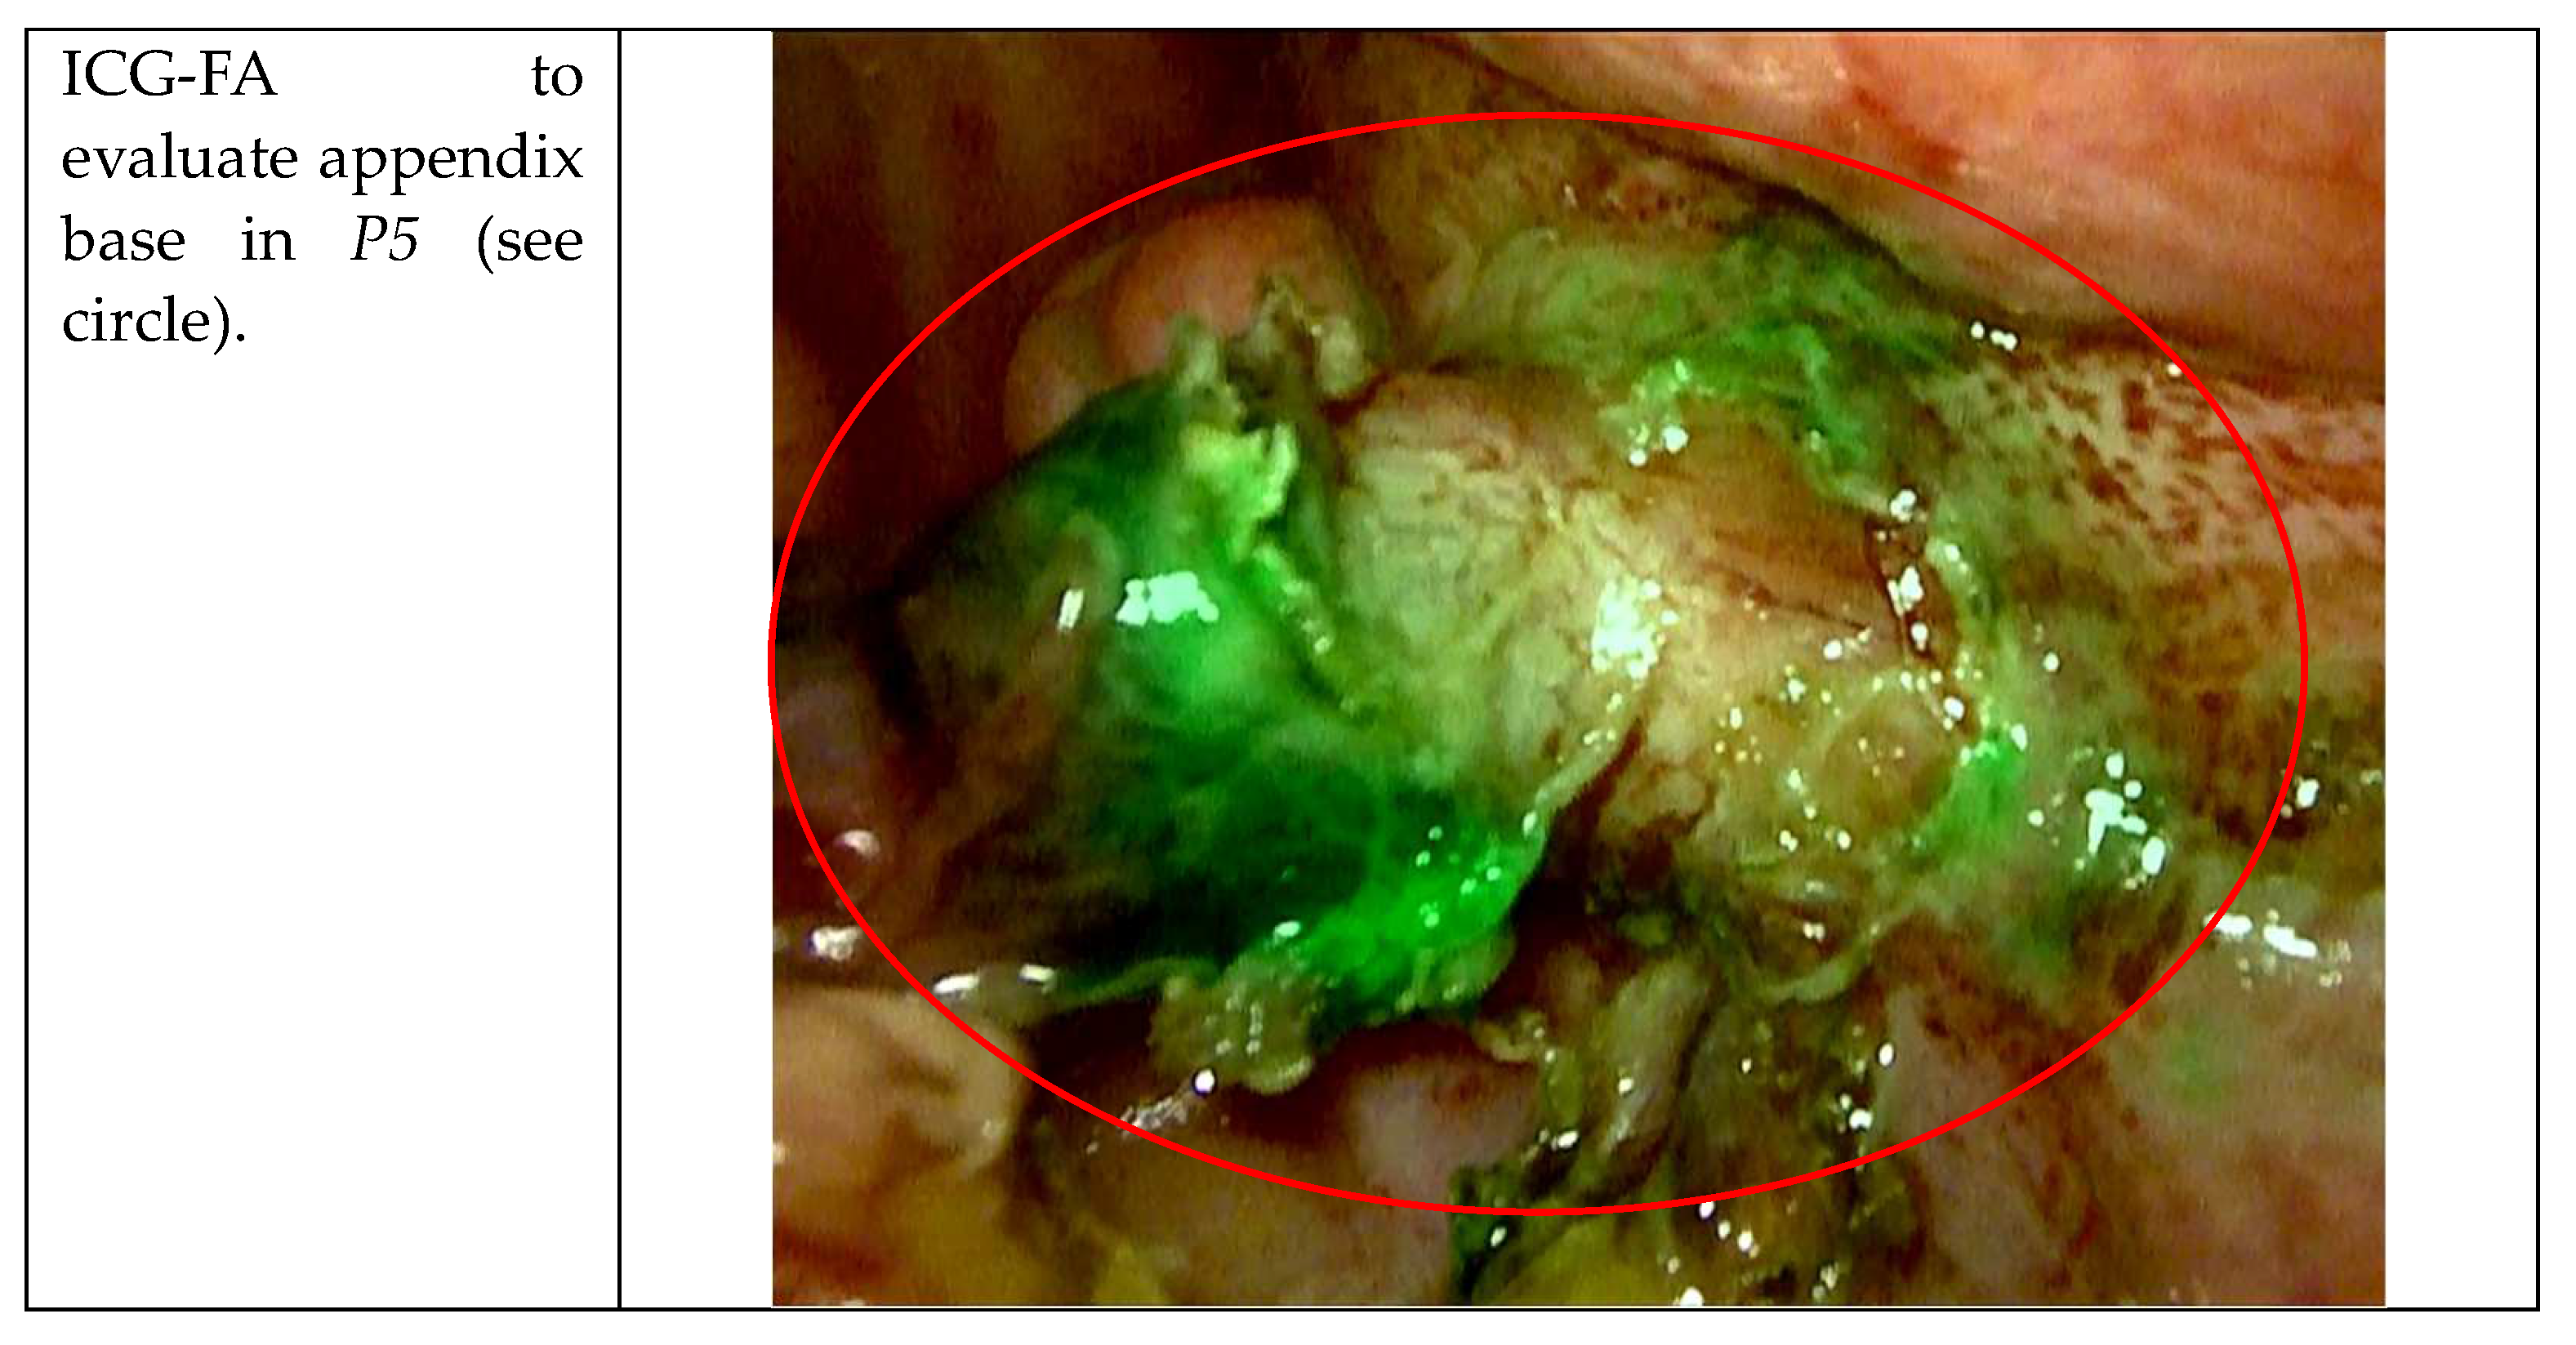

| P5 | M | 65 years | 27.9 | WBC 18.06 109/L, CRP 7.48 mg/dL | No | Caucasian |